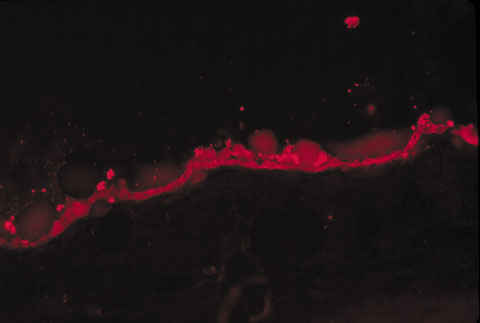

Figura 4

TRASPLANTE DE EPR HUMANO A CONEJO. UN MES TRAS LA CIRUGÍA. SE OBSERVA MONOCAPA DE CÉLULAS MARCADAS CON FLUORESCENCIA ROJA SOBRE LA MEMBRANA DE BRUCH DEL RECEPTOR. CORTE DE CONGELACIÓN SIN TEÑIR (160x).